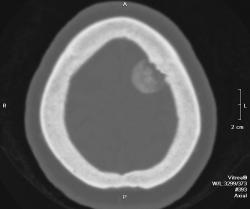

Полностью обызвествленная менингиома теменной области (красная стрелка). В прилегающей кости узурация (зеленые стрелки) и небольшой гиперостоз в виде клюва (голубая стрелка). Небольшой масс-эффект - крыша левого бокового желудочка поддавлена (желтая стрелка), субарахноидальные щели слева немного уже, чем справа. Перифокального отека нет - признак доброкачественности образования. Отек при менингиоме может развиться при очень больших размерах образования или при малигнизации. Пациентка жалуется на головные боли. На снимках черепа ничего необычного нет.